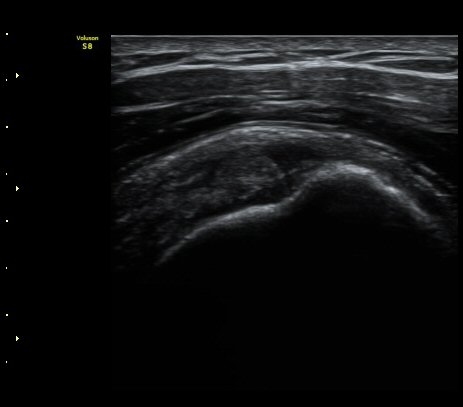

±Ø»ó°Ç Á¾´Ü¸é°Ë»ç¿¡¼­ ´ë°áÀý °Ç ºÎÂøºÎ¿¡ Àú¿¡ÄÚ °Ç °á¼ÕÀÌ °üÂûµÊ

(focal hypoechoic defect of ssupraspinatus tendon at greater tuberosity with

longitudinal scan of subscapularis tendon) »çÁø 4, 5, 6